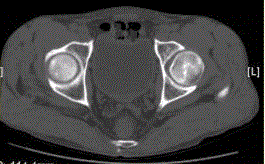

问题 患者男,47岁,左髋部疼痛及压痛6个月,“4”字试验阳性。左髋关节内、外旋活动受限。检查提示:左髋关节活动轻度受限,大腿上部轻压痛。血常规检查正常。髋关节CT及MRI如下图。 股骨头缺血性坏死早期诊断的最佳影像学检查方法是

选项 A.CT B.MRI C.X线平片 D.ECT E.USG F.PETCT

答案 B